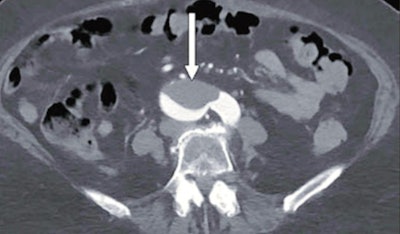

The group found that nine of patients (11%) with COVID-19 had thromboembolic findings on imaging; of these, five had medium to large arterial thrombi. Occurrence of thromboembolic findings in COVID-19 patients compared with those without the disease was statistically significant, at p = 0.02.

"Patients with solid-organ infarction had patent vasculature, suggesting the infarction may have resulted from microthrombi," the group noted.

"COVID-19 may present with medium to large arterial and venous abdominal and extremity macrothrombi," it concluded. "Radiologists should raise concern for COVID-19 when identifying thromboembolic abdominopelvic findings during this pandemic."